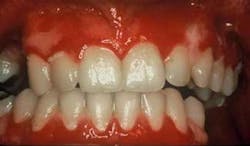

Clinical impressions: As you begin your oral assessment, you note the buccal mucosa and gingiva are erythematous with some ulceration and erosion. The erythema is very prominent at most marginal gingival areas. The tissue bleeds with very little pressure (see figure 1). You also notice that his lips appear ulcerated and crusted (see figure 2).

Early treatment is crucial in controlling pemphigus vulgaris. Sirois, et al. (2000) reported that more than 50 percent of patients in their study sought initial care from their dental clinician. Just as pemphigoid (March 2007) is often characterized as desquamative gingivitis (a general term), this is true also for pemphigus vulgaris depending upon the severity of the disease. The tissue involved is erythematous and ulcerated (see figure 1). Bullae may be present and they rupture to form painful erosions. The borders of the erosions are often ragged and painful. Depending upon the type of pemphigus, the lesions may appear to have vegetations or scales on the surface.